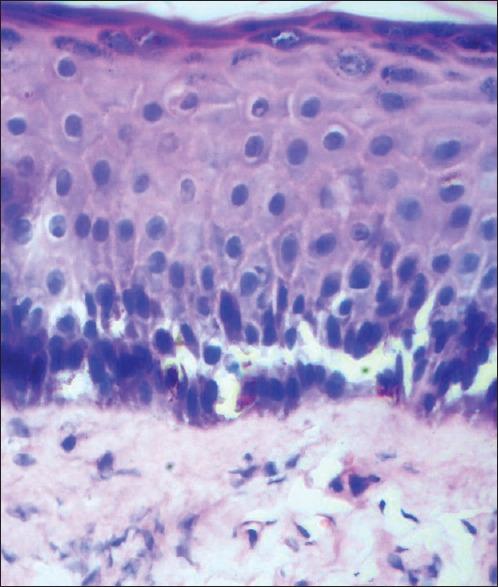

A 42-year-old male developed hemorrhagic bullae and erosions while in alcohol induced coma. The lesions were limited to areas of the body in prolonged contact with the ground in the comatose state. He developed rhabdomyolysis, progressing to acute renal failure (ARF). Histopathological examination of the skin showed spongiosis, intraepidermal vesicles, and necrosis of eccrine sweat glands with denudation of secretory epithelial lining cells. With supportive treatment and hemodialysis, the patient recovered in 3 weeks time. This is the first reported case of bullous lesions and sweat gland necrosis occurring in alcohol-induced coma complicated by rhabdomyolysis and ARF.

一名42岁男性在酒精性昏迷期间出现出血性大疱和糜烂。病变局限于昏迷状态下身体与地面长时间接触的部位。他发生了横纹肌溶解症,并进展为急性肾衰竭(ARF)。皮肤组织病理学检查显示有海绵形成、表皮内水疱以及小汗腺坏死,分泌上皮衬里细胞剥脱。经过支持治疗和血液透析,患者在3周后康复。这是首例报道的酒精性昏迷合并横纹肌溶解症和急性肾衰竭时出现大疱性病变及汗腺坏死的病例。